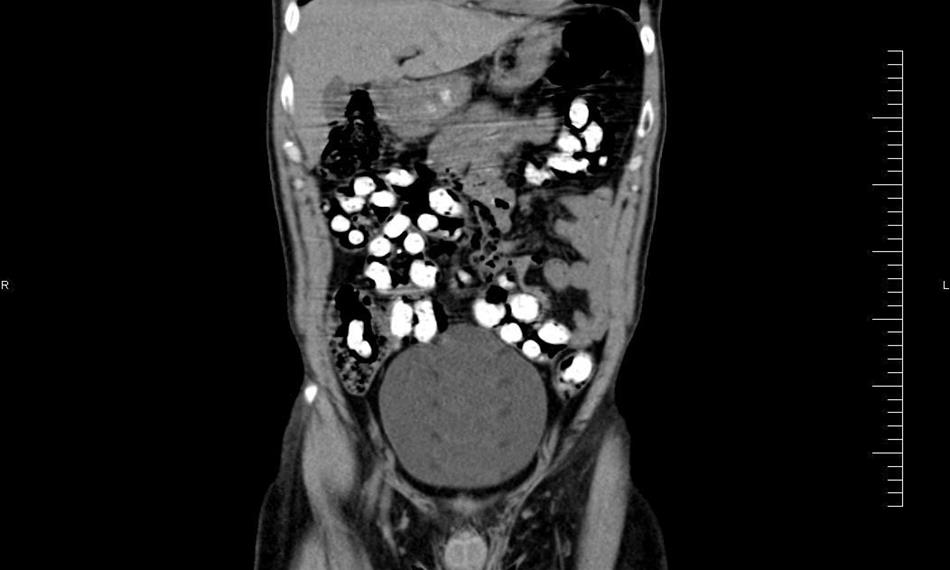

Ke kontrole byl polykač celníky vytipován na základě provedené rizikové analýzy daného letu. Prvotní podezření na pašování drog celníkům potvrdily kontrolní stěry z rukou pašeráka.  Při důkladné kontrole jeho zavazadel a osobní prohlídce nebyly drogy nalezeny, proto bylo provedeno následné rentgenové vyšetření (viz.foto).

Postupně z těla pašeráka vyšlo všech 107 kontejnerků naplněných tuhou hmotou černé barvy. Chemická látka při provedení detekční zkoušky pozitivně reagovala jako opiát. Celková hmotnost všech kapslí včetně drogy je 856 gramů. Určení vlastní hmotnosti a druhu zajištěné drogy je předmětem další odborné expertízy. Podle zkušeností celníků se s největší pravděpodobností jedná o surové opium. Tento druh drogy není na českém trhu obvyklý a zřejmě byla určena k distribuci v jiné zemi.